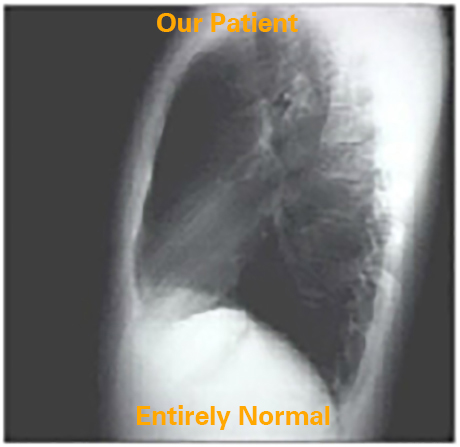

In the lateral chest X ray, anterior aspect of the cardiac silhouette is made up of: the ascending aorta, the right ventricular outflow tract and the right ventricle inferiorly. The posterior margin of the cardiac silhouette is formed by the left atrium above and the left ventricle below.